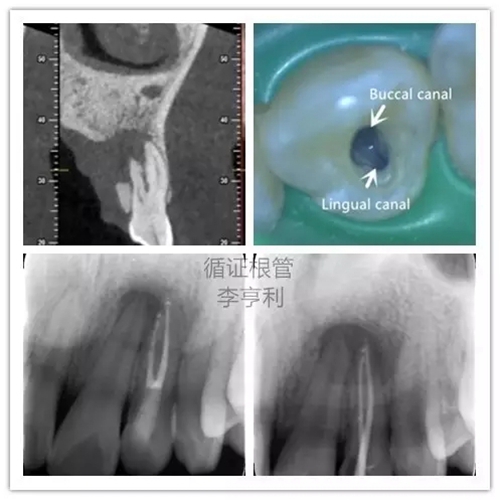

5,根管解剖的評(píng)估

上頜側(cè)切牙擁有雙根管

在CBCT的掃描中,根管形態(tài)能在三維的條件下評(píng)估,能準(zhǔn)確顯示根管數(shù)量和多個(gè)根管之間的聯(lián)系。根據(jù)Matherne et al. (2008)的間接體外研究(ex vivo),牙體牙髓專科醫(yī)生單憑閱讀數(shù)碼X片,即使一個(gè)牙齒進(jìn)行多個(gè)角度拍攝,還是有40%的樣本牙齒出現(xiàn)至少一個(gè)遺漏根管。

對(duì)于最容易被疏忽的上頜磨牙MB2根管,CBCT正確判斷其是否存在的幾率高達(dá)79%,與金標(biāo)準(zhǔn)的牙齒切片(sectioning)準(zhǔn)確率無統(tǒng)計(jì)學(xué)上的區(qū)別(Blattner et al. 2010)。所以,即使對(duì)于非手術(shù)性的根管再治療(non-surgical retreatment),CBCT也能提供巨大的治療價(jià)值。